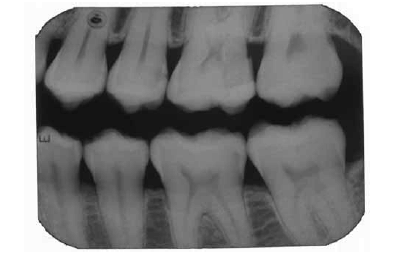

Julgue os itens subsequentes acerca do diagnóstico radiográfico das lesões de cárie dentária, com base na imagem de raio X acima.

O diagnóstico de lesão de esmalte na face distal do dente 34 é compatível com a imagem apresentada.